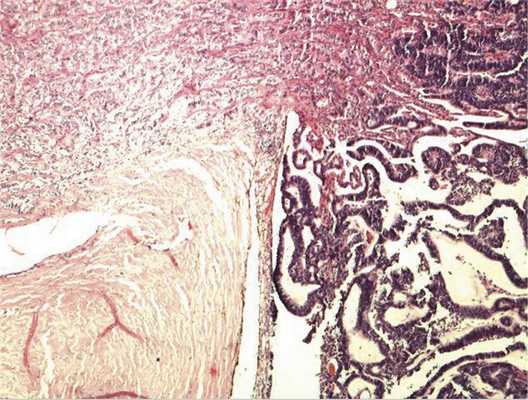

Патоморфологическое исследование. При морфологическом исследовании кусочка новообразования из боковой колодки выявлена опухоль, состоящая из кубических эпителиальных клеток, которые формировали единичные розетковидные структуры и небольшие участки солидного роста. Поставлен предварительный диагноз — недифференцированная ретинобластома без опухолевых комплексов в дистальном отрезке зрительного нерва. Далее при изучении срезов всего глазного яблока выявлен большой опухолевый узел в центральных отделах глазного дна, тесно связанный со зрительным нервом. Узел состоял преимущественно из трубчатых и сетчатых структур, розеток, ленточных образований, что придавало опухоли местами вид «кружева» (рис. 3).

Рис. 3. Часть узла опухоли снаружи от ДЗН, имеющая вид «кружева». Окраска гематоксилином и эозином. Ув. 100.

Отмечалось наличие ленточных структур из низкодифференцированных эпителиальных клеток (рис. 4). Параллельно встречались участки солидного строения из клеток с гиперхромными ядрами с признаками клеточного и ядерного полиморфизма. В них почти исчезает строма, появляются митозы, встречаются участки дистрофии и некроза (рис. 5). Опухоль врастает в ткань ДЗН с переходом за laminacribrosa, но не достигает линии отсечения (рис. 6). В таком виде опухоль обладает местнодеструирующим характером роста и может давать метастазы, глубоко инфильтрируя прилежащую к ДЗН ткань хориоидеи. Окончательный гистологический диагноз: злокачественная медуллоэпителиома центрального отдела сетчатки с вовлечением ДЗН и инвазией перипапиллярной хориоидеи, с глубоким прорастанием по зрительному нерву, не достигая линии отсечения.